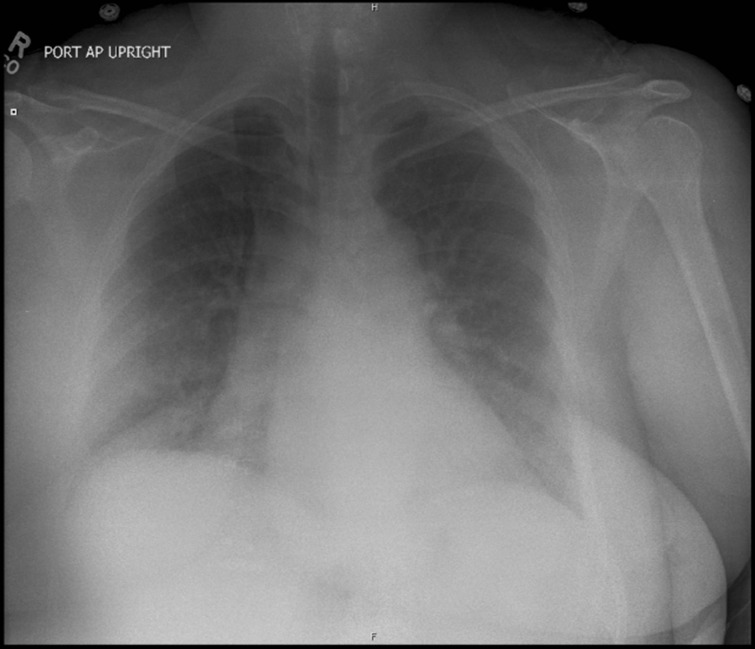

Chest X-ray (CXR) showed pulmonary edema (Fig. 1).

Figure 1.

Chest X-ray showing pulmonary edema.